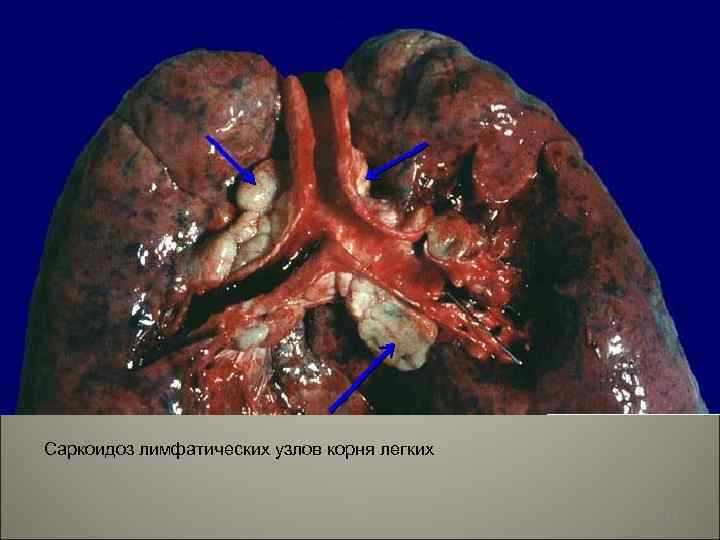

• При внутригрудной форме поражаются лимфоузлы средостения, бронхи и легкие, постепенно развивается диффузный пневмосклероз и легочное сердце, что может явиться причиной смерти. Внегрудная форма характеризуется полиморфностью поражений, может повреждаться любой орган, кроме надпочечников. Чаще поражаются шейные лимфоузлы, кожа, слюнные железы (особенно околоушные).

Саркоидоз лимфатических узлов корня легких 44